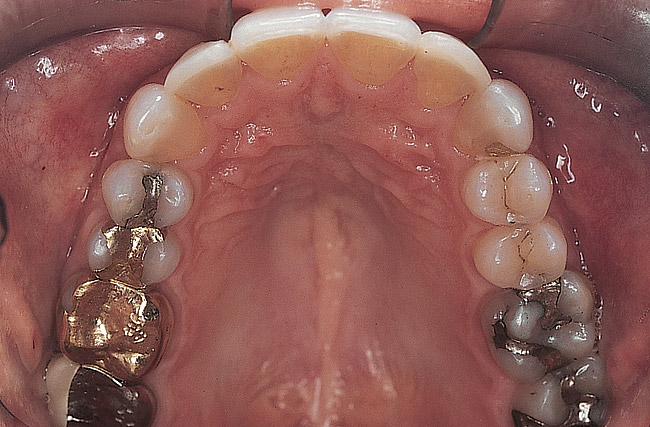

Figure 2  Preoperative maxillary occlusal view.

Figure 2